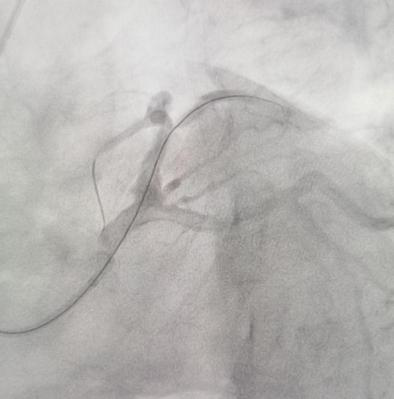

迅速完成穿刺并顺利送入造影导管后,造影结果却给术者一个大大的难题:患者前降支近段完全闭塞,开口近段瘤样扩张,直径约6-7mm,几乎就是正常人的两倍。快速通过导丝,执行血栓抽吸操作,血管得以重新畅通。然而病变位于真分叉处,第一对角支的直径仅约3.5mm,且开口处有高达90%的狭窄。面对这一情况,精准的治疗方案依赖于丰富的经验分析:是采用单支架策略?还是双支架?或者尝试球囊拘禁技术?但主支直径过大,无合适支架。李绍波主任经过短暂快速地思考后,决定使用药物球囊!

李绍波主任当机立断,将指引导丝送入分支。在普通导丝无法通过的情况下,转而使用CTO导丝,成功抵达对角支的远端。随后,依次运用小球囊、大球囊、切割球囊及药物球囊进行操作。在最大型号4.0的药物球囊完成血管扩张后,介入室内的人员均感到紧张情绪得以缓解。手术效果良好,患者的心率逐步稳定,呼吸困难的状况亦有所改善。